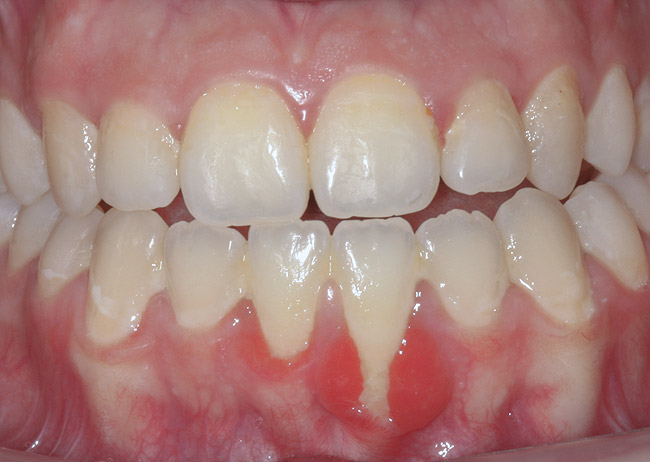

CASE 2 Fig 4. Post-orthodontic Miller Class II recession for which orthodontic treatment was not recommended. Clinical view 3 years after orthodontic treatment, showing relapse in teeth alignment and GR on lower left central incisor.

Figure 4

In cases with thin lingual bone, as measured on CBCT (<2.5 mm at a level of 8 mm apical to the CEJ), orthodontic treatment is not advisable, leaving surgical root coverage as the only option. However, the prognosis for this procedure is poorer, because the predominant cause is not addressed. Figure 4 shows the frontal clinical view of a patient with a hyperdivergent growth pattern who presented with post-orthodontic GR of a labially displaced lower central incisor. The sagittal CBCT view (Figure 5) shows complete absence of lingual bone, which contraindicated orthodontic tooth repositioning.